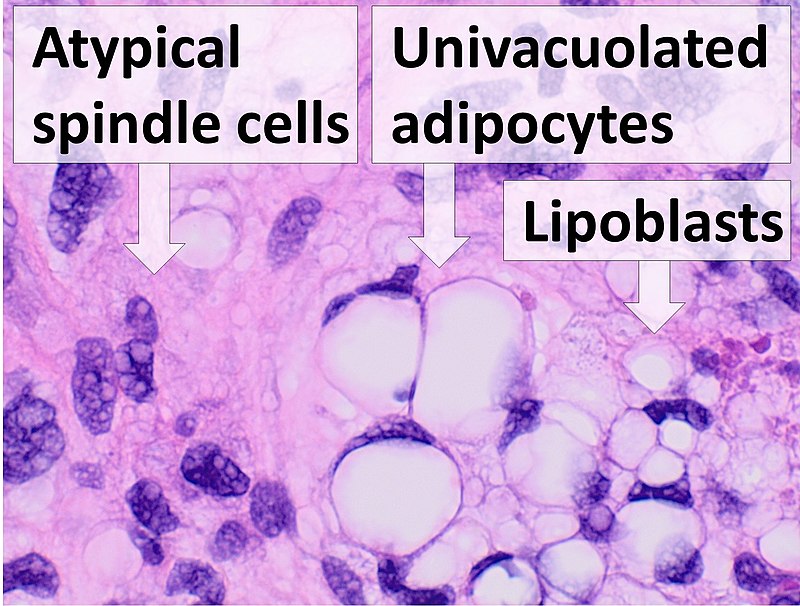

Liposarcoma

Liposarcomas are malignant tumors of adipose tissue.

Definitive diagnosis of liposarcoma is made by pathology showing malignant proliferation of adipose tissue.

Lipoblasts are the characteristic cells seen in liposarcoma.